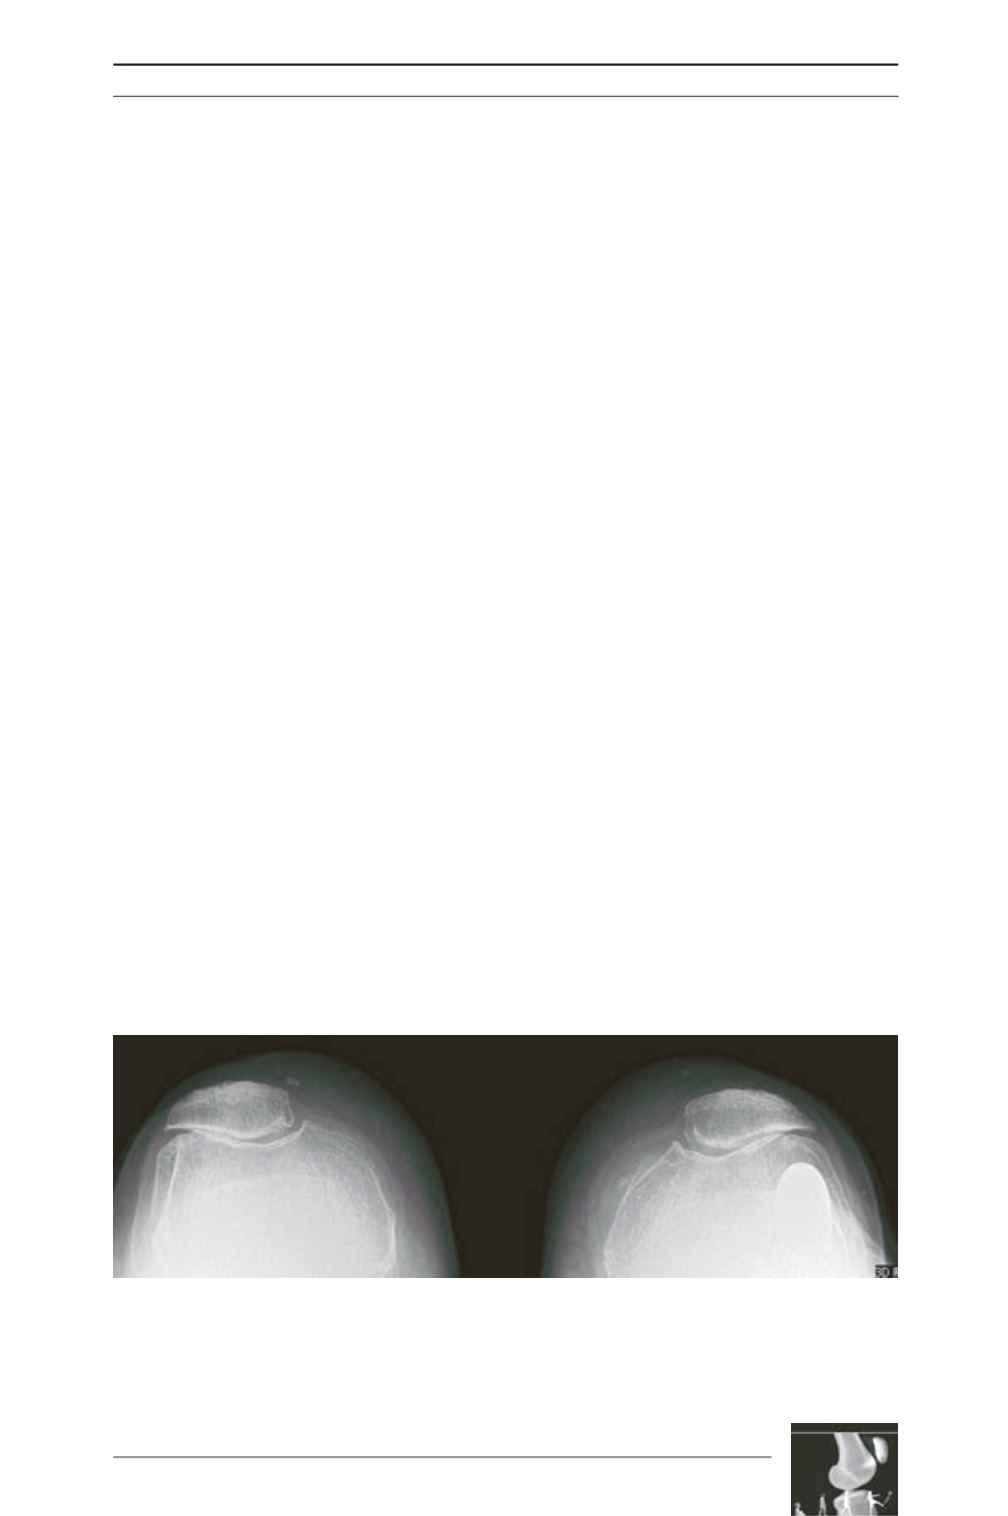

Progression of patellofemoral arthritis was

observed in 2 cases: one level 1 (3 years

follow-up) and one level 2 (7 years follow-up)

of the classification of Iwano (fig. 1, 2).

Fig. 1: Postoperative patellofemoral OA grade 2 (7 years follow-up).